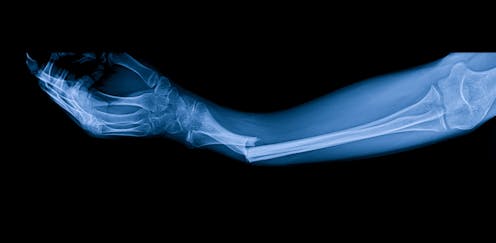

Osteoporosis affects about 3.8 million people in the UK. The disorder causes bones to become fragile due to low bone mass and deterioration in bone structure. This makes them more likely to break.

The risk of developing osteoporosis increases with age – and is especially common in women after the menopause. This is because their oestrogen levels decrease. Oestrogen is protective to bones, as it slows down the natural bone breakdown. Around half of women over 50 will experience a bone fracture.

Fractures can have severe consequences – including chronic pain, loss of independence and even increased risk of death. Abaloparatide is a new addition to the osteoporosis-fighting arsenal which will greatly benefit people with a very high risk of fracture.